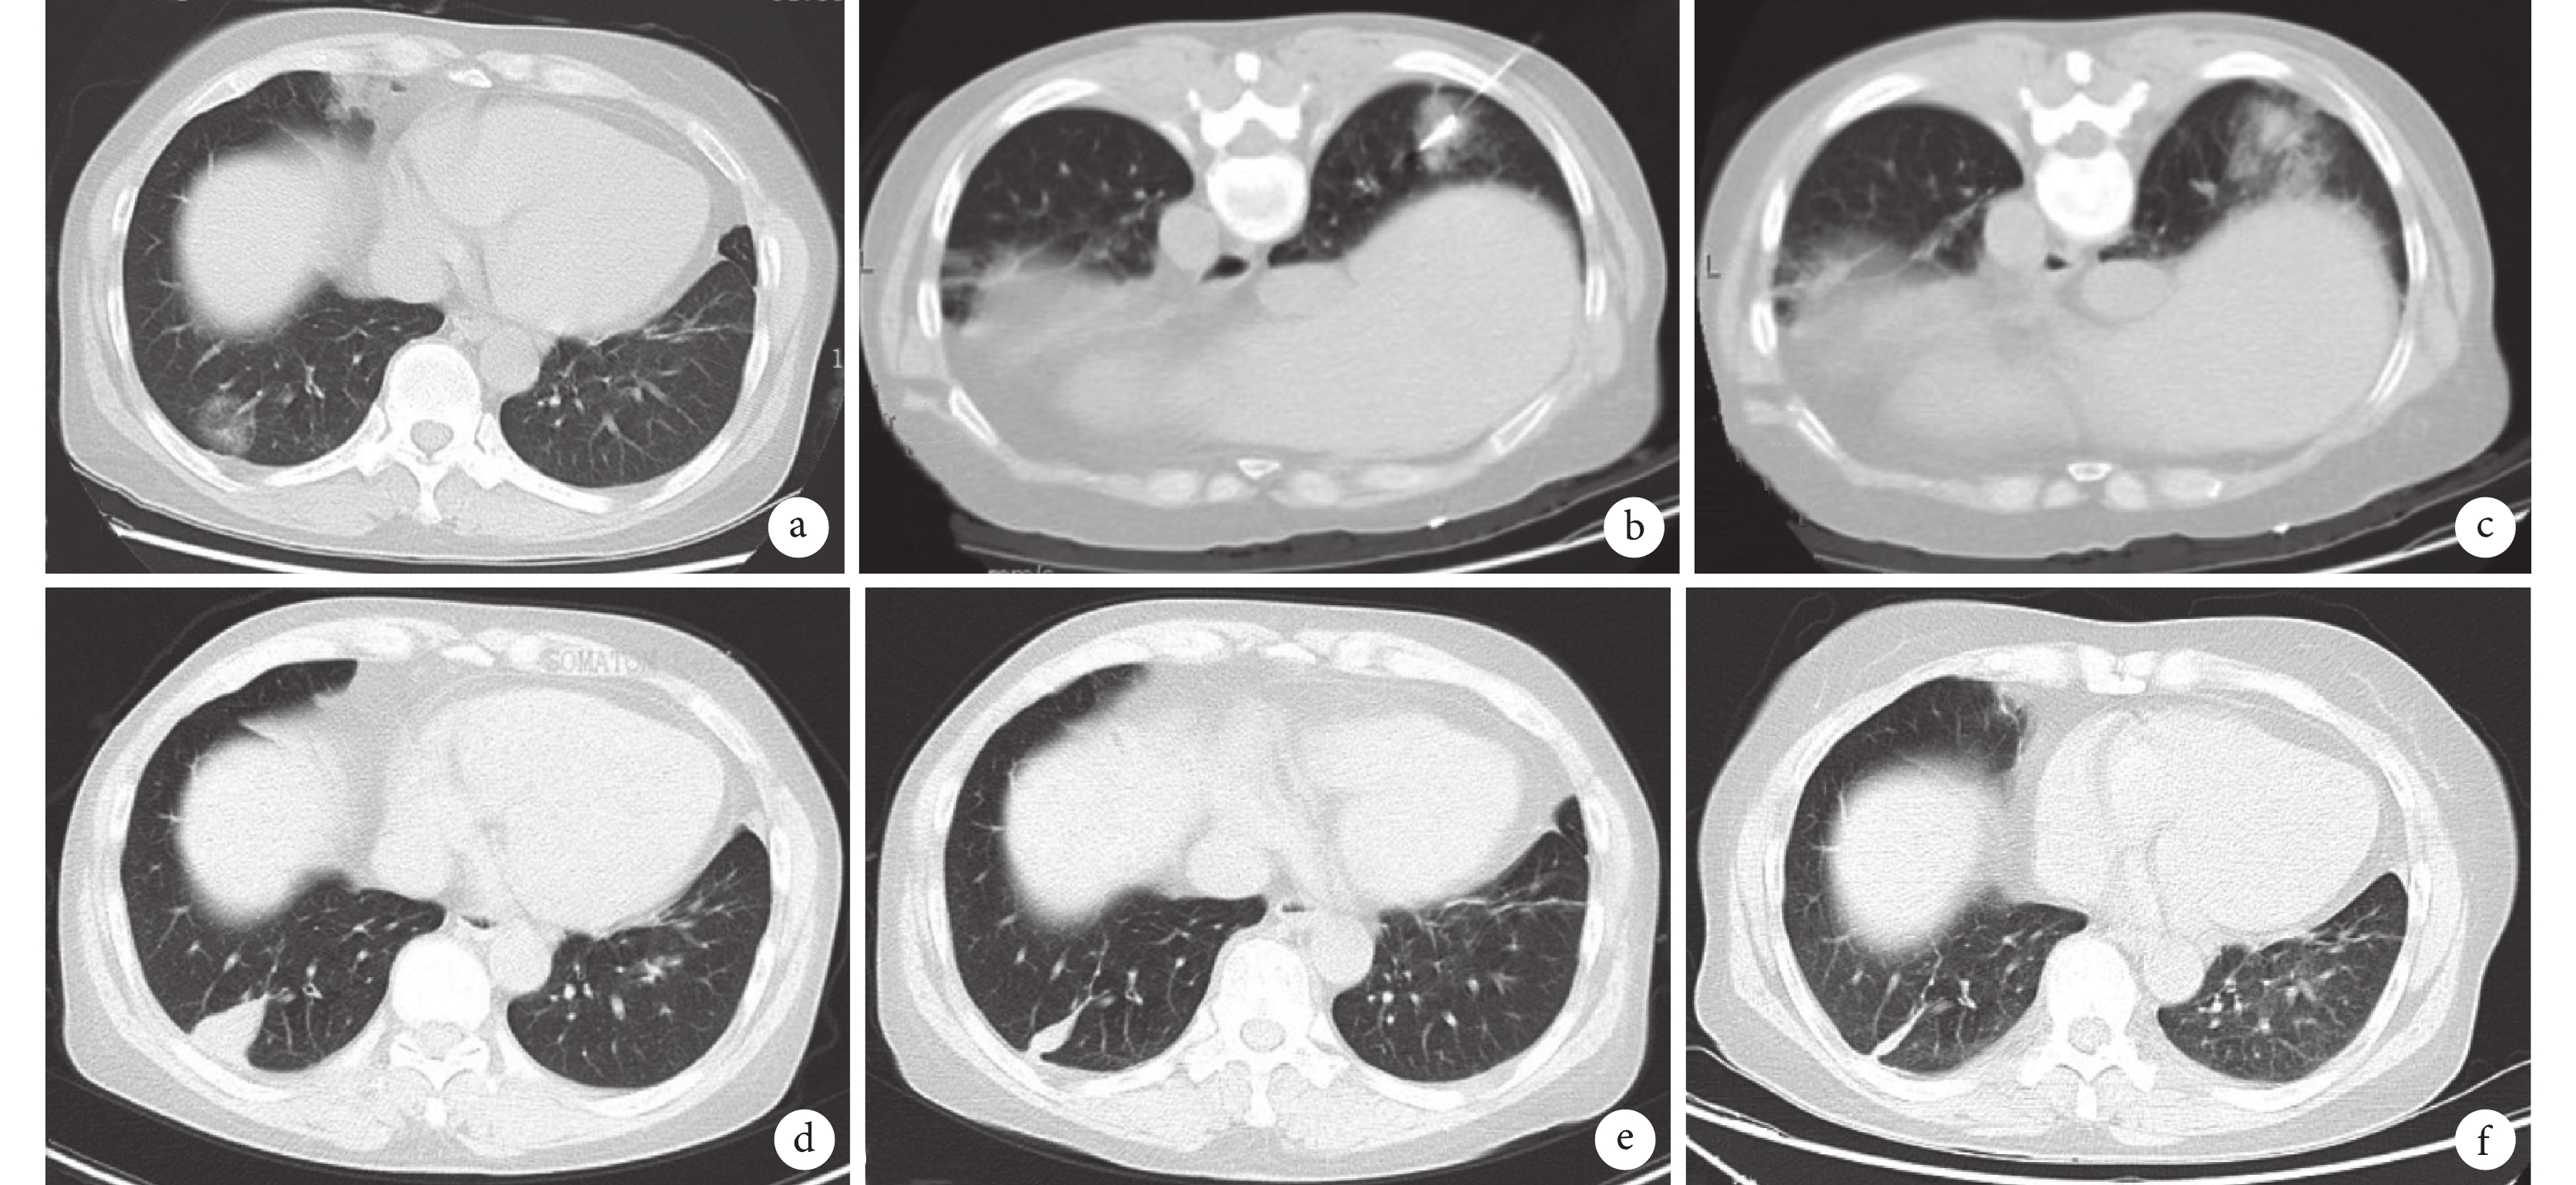

以上研究結果為消融治療GGN提供了初步的循證醫學證據,提示通過消融技術介入根治GGN型肺癌是可行的,且操作安全。需要指出的是,這些臨床研究的隨訪時間相對較短,病例數較少,尚缺乏大樣本、前瞻性臨床研究的數據。相信未來會有更多大樣本、多中心、前瞻性、長隨訪的研究,以提供高級別循證醫學證據。而且,雖然消融治療有根治大部分GGN型肺癌的可能,但其無法進行淋巴結清掃或治療,所以并不意味著消融治療可以替代外科手術。本中心也對一些符合條件的GGN型肺癌病例進行了經皮消融治療,積累了一定的經驗,在臨床中驗證了GGN介入根治的可行性,典型病例見圖2~4。

女,62歲,右肺下葉GGN隨訪中增大,經皮穿刺活檢確診腺癌,拒絕外科手術;a:治療前右肺下葉2.5 cm的mGGN;b:經皮微波消融(功率40 W、時間8 min);c:消融后暈影明顯大于病灶;d:微波消融治療3個月后影像表現;e:微波消融治療16個月后病灶明顯縮小;f:微波消融治療30個月后病灶僅殘留纖維條索影